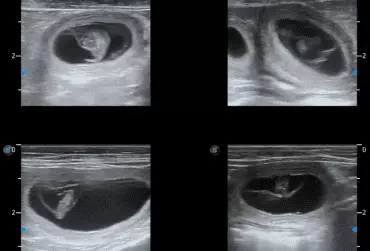

W literaturze opisano niewiele przypadków ciąż bliźniaczych jednokosmówkowych u suk. W trakcie wczesnej diagnostyki ultrasonograficznej ciąży u suki rasy whippet (chart angielski) zobrazowano pęcherz ciążowy, w którym znajdowały się dwa zarodki. Podczas badań kontrol­nych zarodki, a później płody wykazywały prawidłową organogenezę i żywotność. Ich rozwój przebiegał podobnie względem pozostałych ośmiu płodów. W 63. dniu ciąży wykonano zabieg cesarskiego cięcia i wydobyto dwa płody tej samej płci, o bardzo podobnym wyglądzie, z dwóch pęcherzy płodowych przyczepionych do jednego łożyska, oraz pozostałe osiem płodów.

Ryzyko związane z ciążą bliźniaczą jednokosmówkową u ciężarnych suk nadal jest nieznane, istnieją jednak doniesienia o śmierci płodu lub płodów w ciążach jednokosmówkowych u tego gatunku. Badanie ultrasonograficzne w czasie ciąży pozwala na wczesne rozpoznanie ciąży jednokosmówkowej, a monitorowanie żywotności płodów może ograniczyć ryzyko powikłań położniczych i przynieść korzyści zdrowotne zarówno samicy, jak i rodzeństwu z miotu.